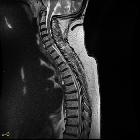

Disc protrusions are a type of disc herniation characterized by protrusion of disc content beyond the normal confines of the intervertebral disc, over a segment less than 25% of the circumference of the disc. The width of the base is wider than the largest diameter of the disc material which projects beyond the normal disc margins. The protrusion must not extend above or below the relevant vertebral endplates .